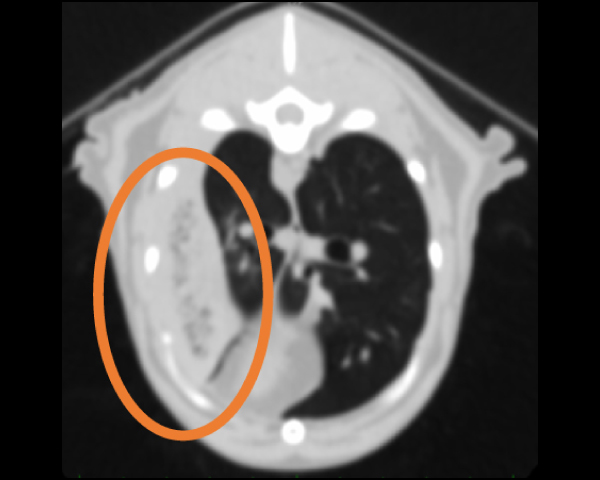

CT検査にて肺野のマイクロバブル所見

エンドGIAを用いた肺葉切除